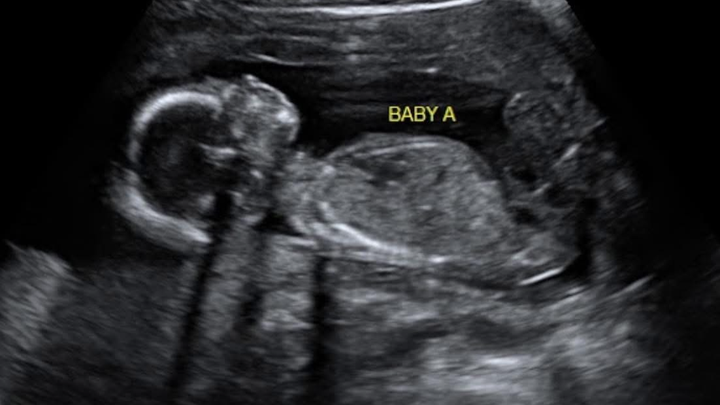

My name is Cindy Arnold and my daughter and son in law, Kara and Perry Stevens, are expecting our first grandbabies....TWINS! One boy, Walt, and one girl, Lumi.

On Monday, March 31st, Kara and Perry went to the doctor for a routine anatomy scan ultrasound at 21 weeks. Everything looked great with Walt and Lumi until the tech got to Walt’s heart. Unfortunately, only the right side of Walt’s heart developed in the womb, and he’s been diagnosed with HLHS. This is a rare but very serious heart defect that would result in death shortly after birth without a series of surgeries. What was once going to be a natural home birth is now going to involve Kara moving to Durham, NC five weeks before her due date to prepare to give birth to Walt and Lumi at Duke, where Walt will be surrounded by some of the top pediatric cardiologists and children’s surgeons in the country. The tentative plan is for him to have his first surgery 5-10 days after birth, his second surgery at 4 months old, and his third around 4 years old. He will likely still need a heart transplant around 20-30 years old.